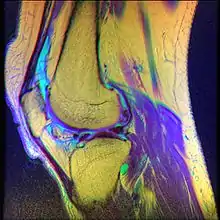

Diagnostic methodMRI

• Magnetic Resonance Imaging (MRI) – to observe cartilage condition and assess deterioration